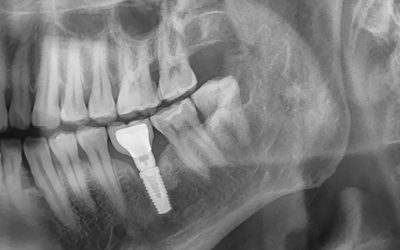

Les implants dentaires et la santé osseuse : ce que vous devez savoir

Les implants dentaires sont une solution populaire et efficace pour remplacer les dents manquantes. Cependant, avant de procéder à l’implantation, il est crucial de prendre en compte la santé de votre os.En effet, les implants nécessitent un os de mâchoire...